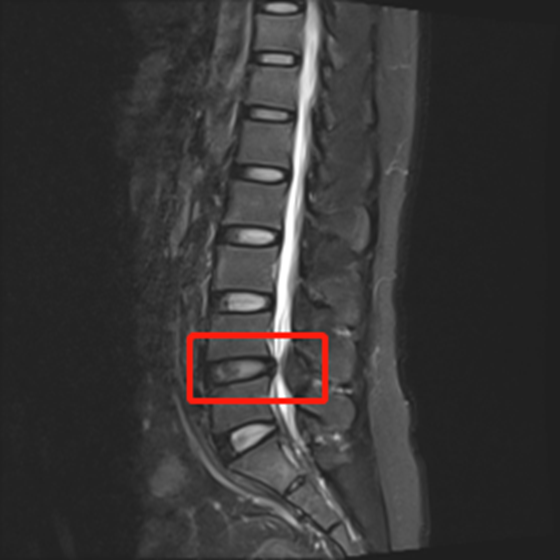

47岁女性患者,因为腰痛和双下肢麻痛长达五年来到湘雅常德医院就诊,其近期活动后双下肢麻痛症状更明显,严重影响生活质量。脊柱外科医师团队对患者进行全方位检查,诊断为“L4-5椎间盘突出合并椎管狭窄”。先对患者展开保守治疗后,效果不明显。经过周密讨论和评估,为患者制定了脊柱微创治疗方案——采用内镜技术下单侧入路“双侧黄韧带切除、髓核摘除、中央椎管减压术。”在麻醉手术部等科室的大力配合下,脊柱外科团队中的陈芳田主任医师、刘磊主治医师、向思宇主治医师合作顺利完成了该手术。患者术后第二天即可下床活动,间歇性跛行症状完全缓解。术后一周即可自由活动,术后一个月复查,患者非常满意微创手术治疗带来的快速康复的效果。

手术前